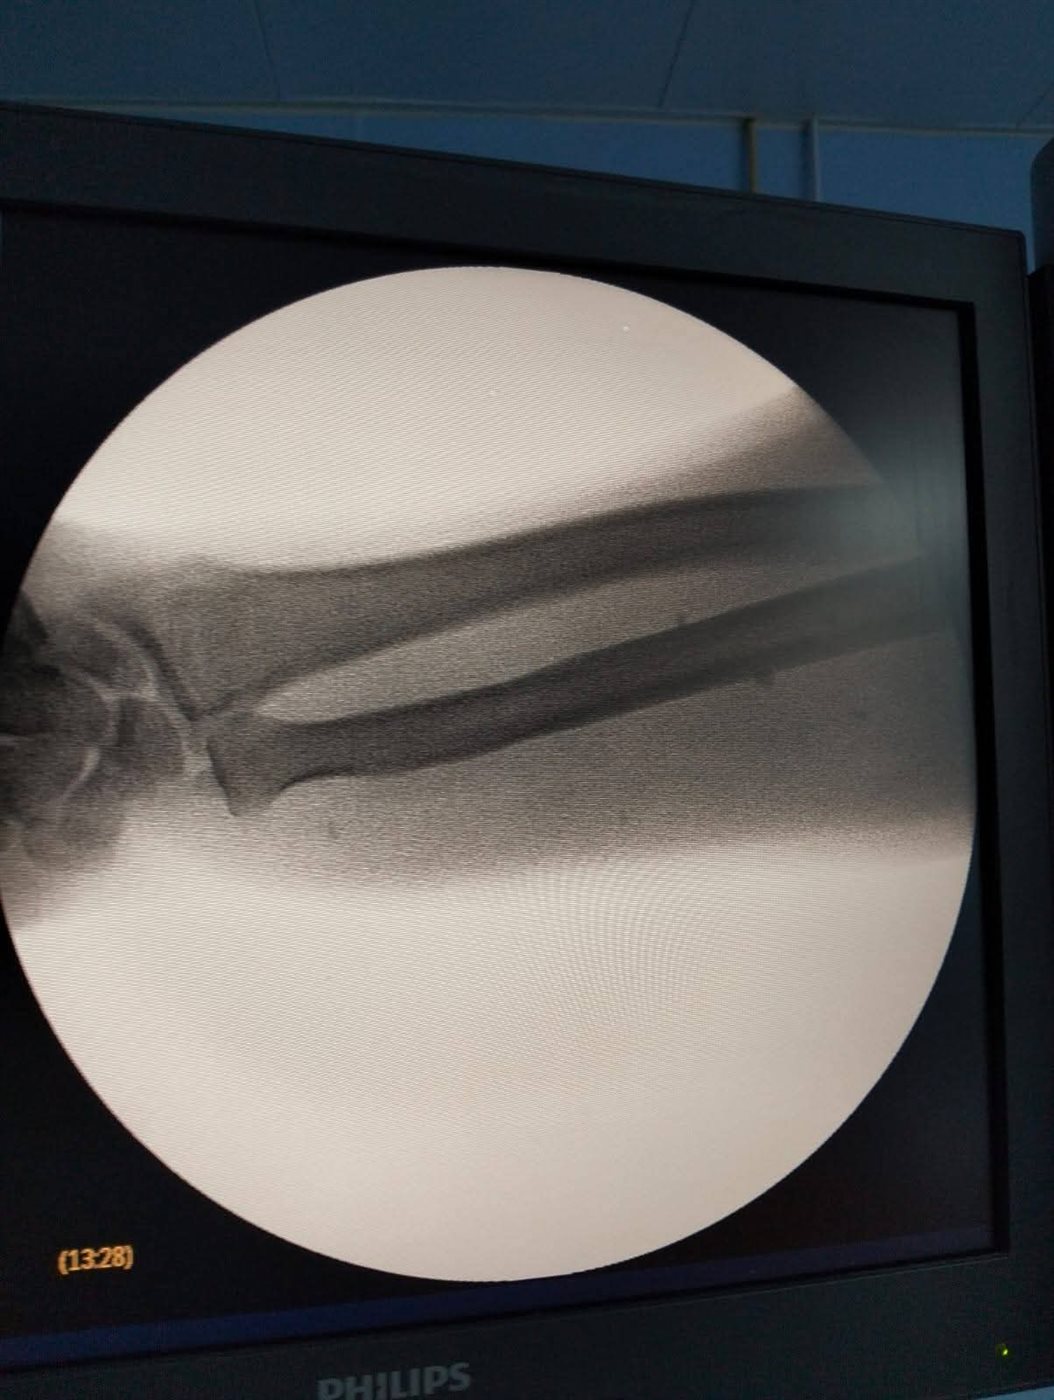

وشهدت غرف العمليات بمستشفى السنبلاوين العام تنفيذ قائمة عمليات متنوعة خلال يوم عمل واحد، شملت جراحات دقيقة في تخصصات الجراحة العامة، والنساء والتوليد، وجراحة التجميل، والأنف والأذن، وجراحة العظام، وجراحة المخ والأعصاب، حيث تم إجراء استئصال مرارة بالمنظار، واستئصال زائدة دودية، واستئصال رحم، إلى جانب ولادات قيصرية وطبيعية، فضلًا عن تدخلات تجميلية لعلاج التهتكات والجروح، واستئصال لوز ولحمية وغضاريف أنف، والتعامل مع كسور متعددة وخلع مفاصل وقطع أوتار ورفع مسامير عظمية، بالإضافة إلى تدخل جراحي دقيق لحالة نزيف بالأم الجافية بالمخ، وذلك وسط تكامل كامل بين الفرق الطبية والتمريضية وأطقم العمليات.